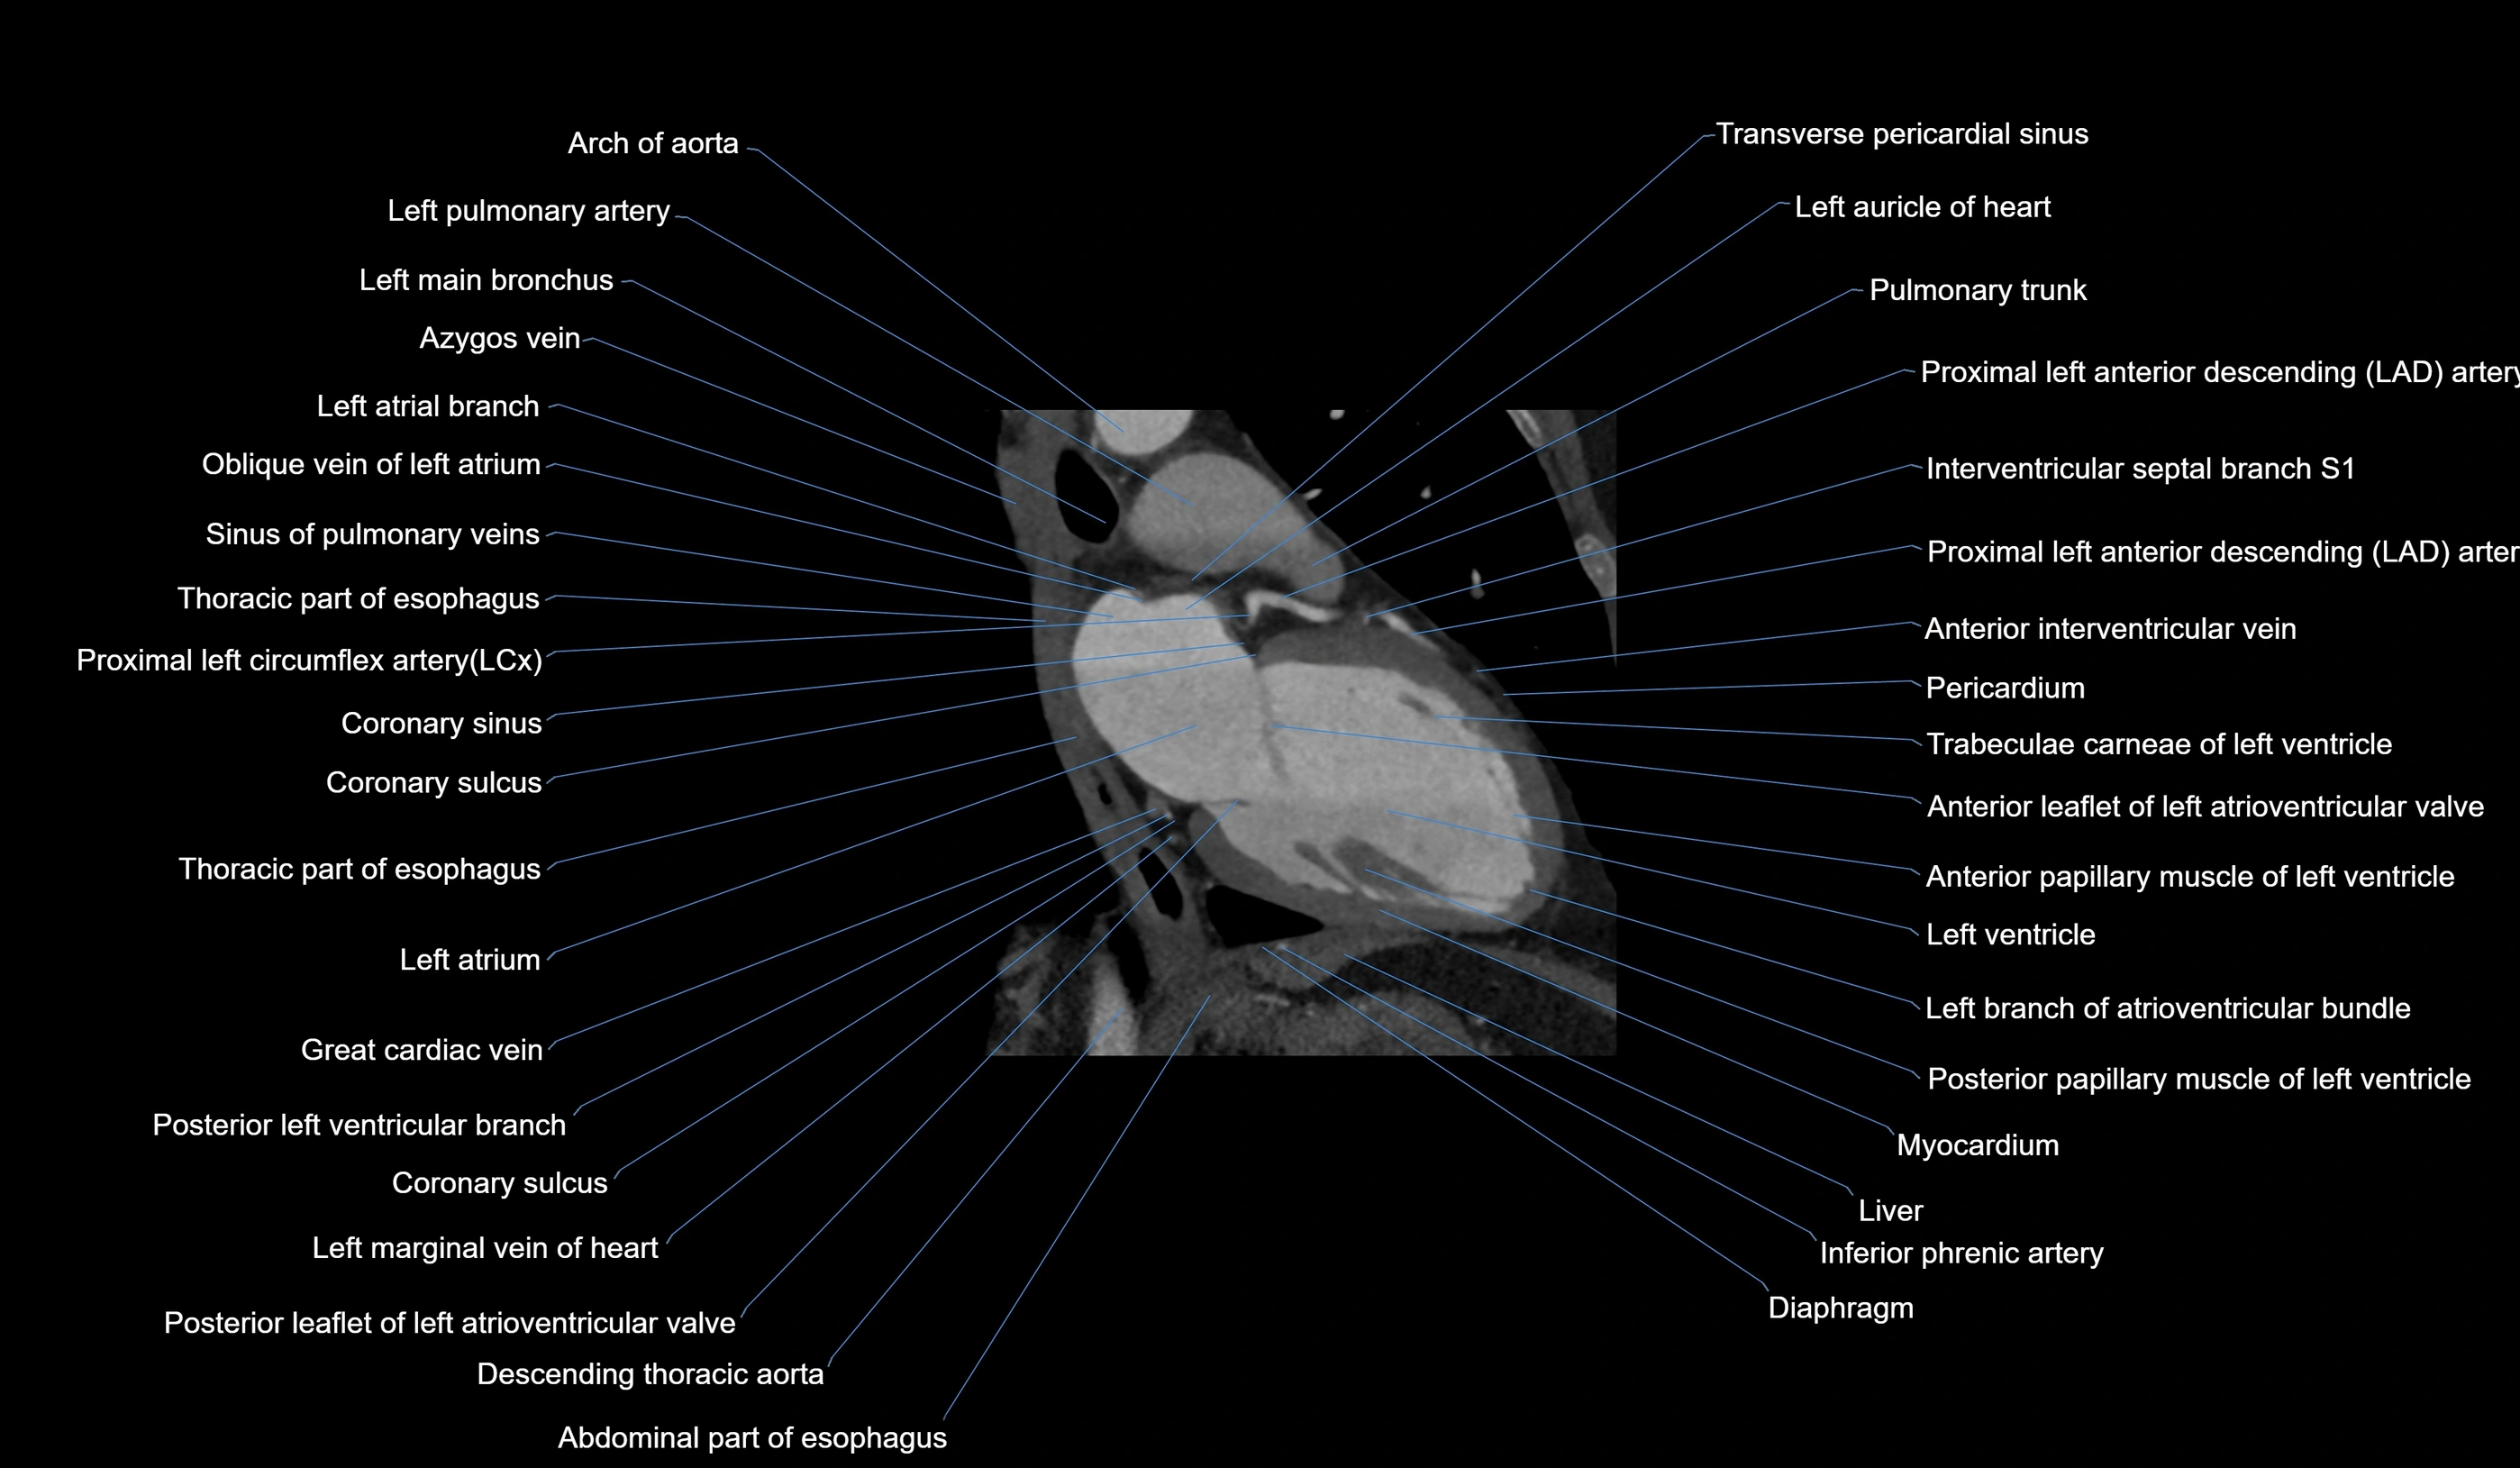

CT images